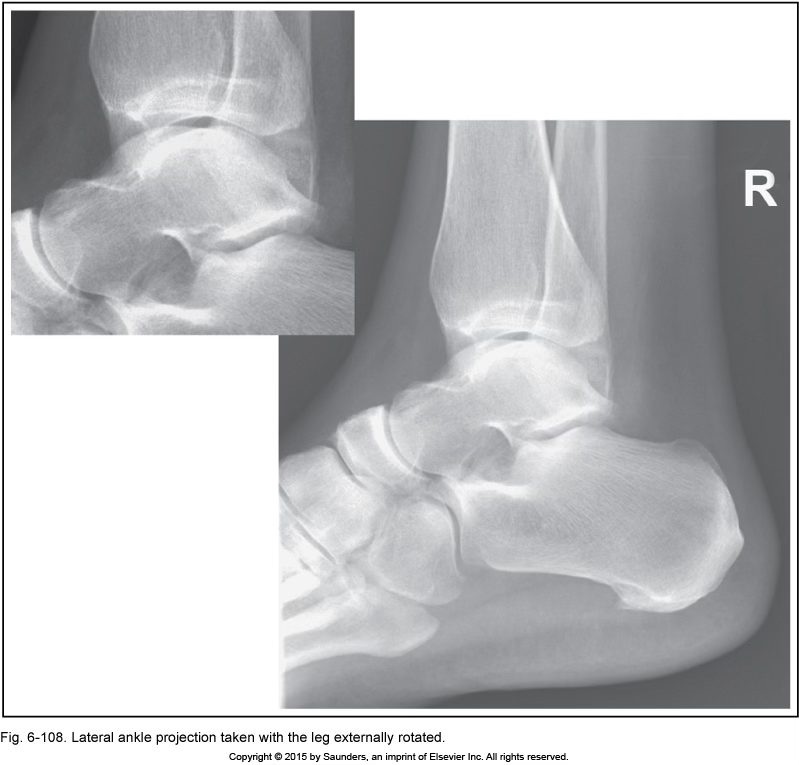

leg externally rotated

sinus tarsi more open

fibula at the back of tibia